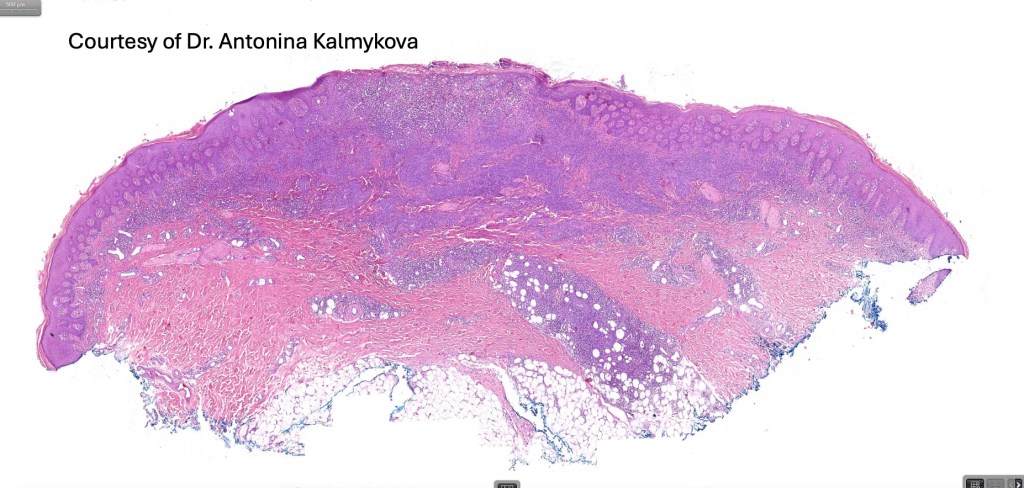

Histological features

The histological hallmark of mycosis fungoides is the presence of large atypical lymphocytes with a convoluted/cerebriform nuclear border (Sézary cells). These may be found at the epidermal-dermal jnuction and as collections within the epidermis (Pautrier microabscess). These are most easily found in plaque stage disease. The epidermal component can be subtle in patch stage disease and is often lost in tumor stage dsease. The classification into patch, plaque & tumor stage disease is less helpful histologically as the features merge from one to the other. It is all a matter of degree.

Patch stage disease

•Changes can be subtle & dependent on clinicopathological correlation; in many patients sequential biopsies over many months may be necessary to establish the diagnosis.

•Mild hyperkeratosis & focal parakeratosis, acanthosis, epidermal atrophy or of normal thickness

•Superficial dermal lymphocytic infiltrate containing variable numbers of Sézary cells with atypical, irregular, hyperchromatic nuclei surrounded by a halo; these can be very few in number and dependant on viewing multiple levels

•Palisading of atypical lymphocytes along the epidermal-dermal border

•Pautrier microabscesses may be present but are often absent in patch stage disease

•Variable interface change with keratinocyte necrosis & pigmentary incontinence

•Eosinophils & plasma cells sometimes present

•Coarse collagen bundles in the papillary dermis can be a feature but this is not as marked as seen in plaque disease

.Although in typical mycosis fungoides fungoides, spongiosis is absent, exceptionally it can be a feature

Plaque Stage Disease